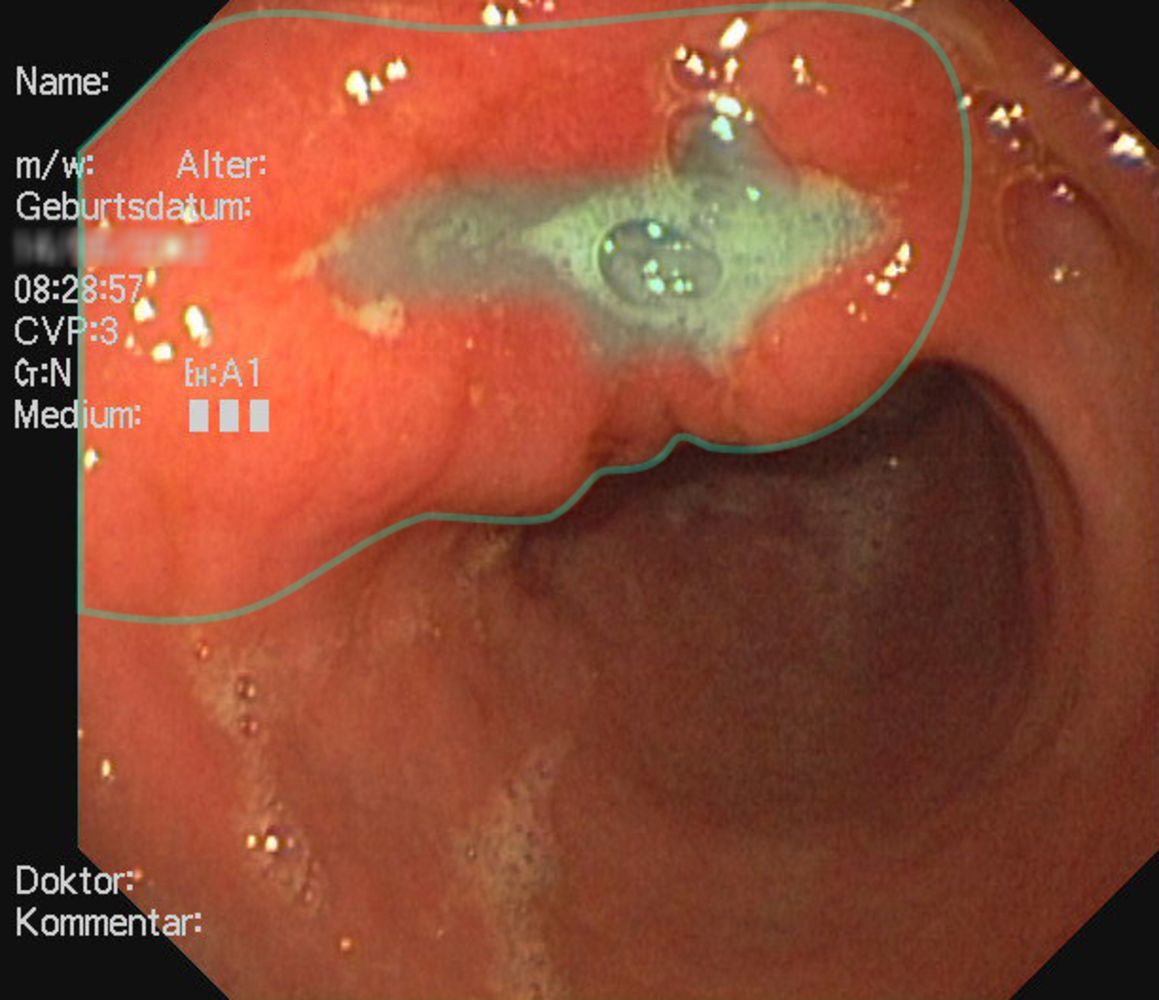

Endoscopy view of the gastric antrum

There is a gastric mass at the level of the lesser curvature with an irregular margin (perimeter marked by green outline) and central ulceration (green overlay).

These findings are consistent with gastric cancer.